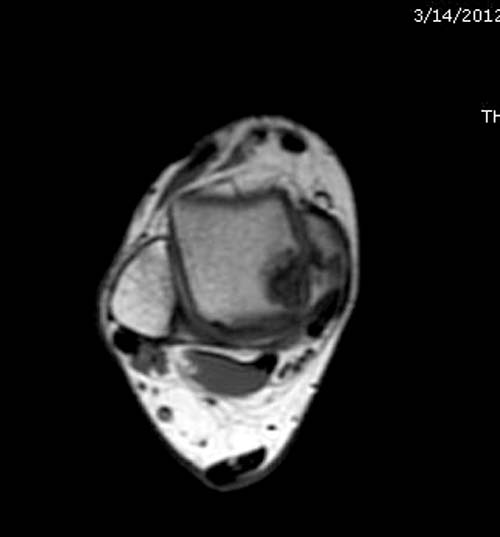

Разбираемый случай не имеет ничего общего с классическим Аваскулярным Некрозом Таранной кости. Здесь так назывемый (osteochondral defect) или osteochondritis dissecans (OCD) таранной кости, при котором патология локализуется в медиально-верхнем нагрузочном отделе. В основном OCD

встречается после хронической травмы, но бывают случаи врожденного генеза, которые обнаруживаются при случайных исследованиях.

Симптоматология  OCD выражается слабым отеком, а более сильные боли наступают после физической нагрузки. В отличие от АВН тарана, когда боли постоянные, а при OCD боли изчезают после отдыха. В начальных стадиях

на рентгенограммах не всегда заметны склерозные участки, и поэтому в большинстве диагноз устанавливается поздно. Приход КТ и МРТ улучшил диагностику, и в срезах внутри кисты можно увидеть жидкость, но это не означает проявление симптоматологии. Симптомы проявляются с момента образования внутрисуставных краевых фрагментаций!

Вложение не в текстовом формате было извлечено…

Имя     : 8 OCD MRI.jpg

Тип     : image/jpg

Размер  : 40549 байтов

Описание: отсутствует

Url     : http://weborto.net:8080/pipermail/ortho/attachments/20120408/bb356219/attachment-0019.jpg

Имя     : 10 OCD MRI.jpg

Размер  : 33644 байтов

Url     : http://weborto.net:8080/pipermail/ortho/attachments/20120408/bb356219/attachment-0020.jpg